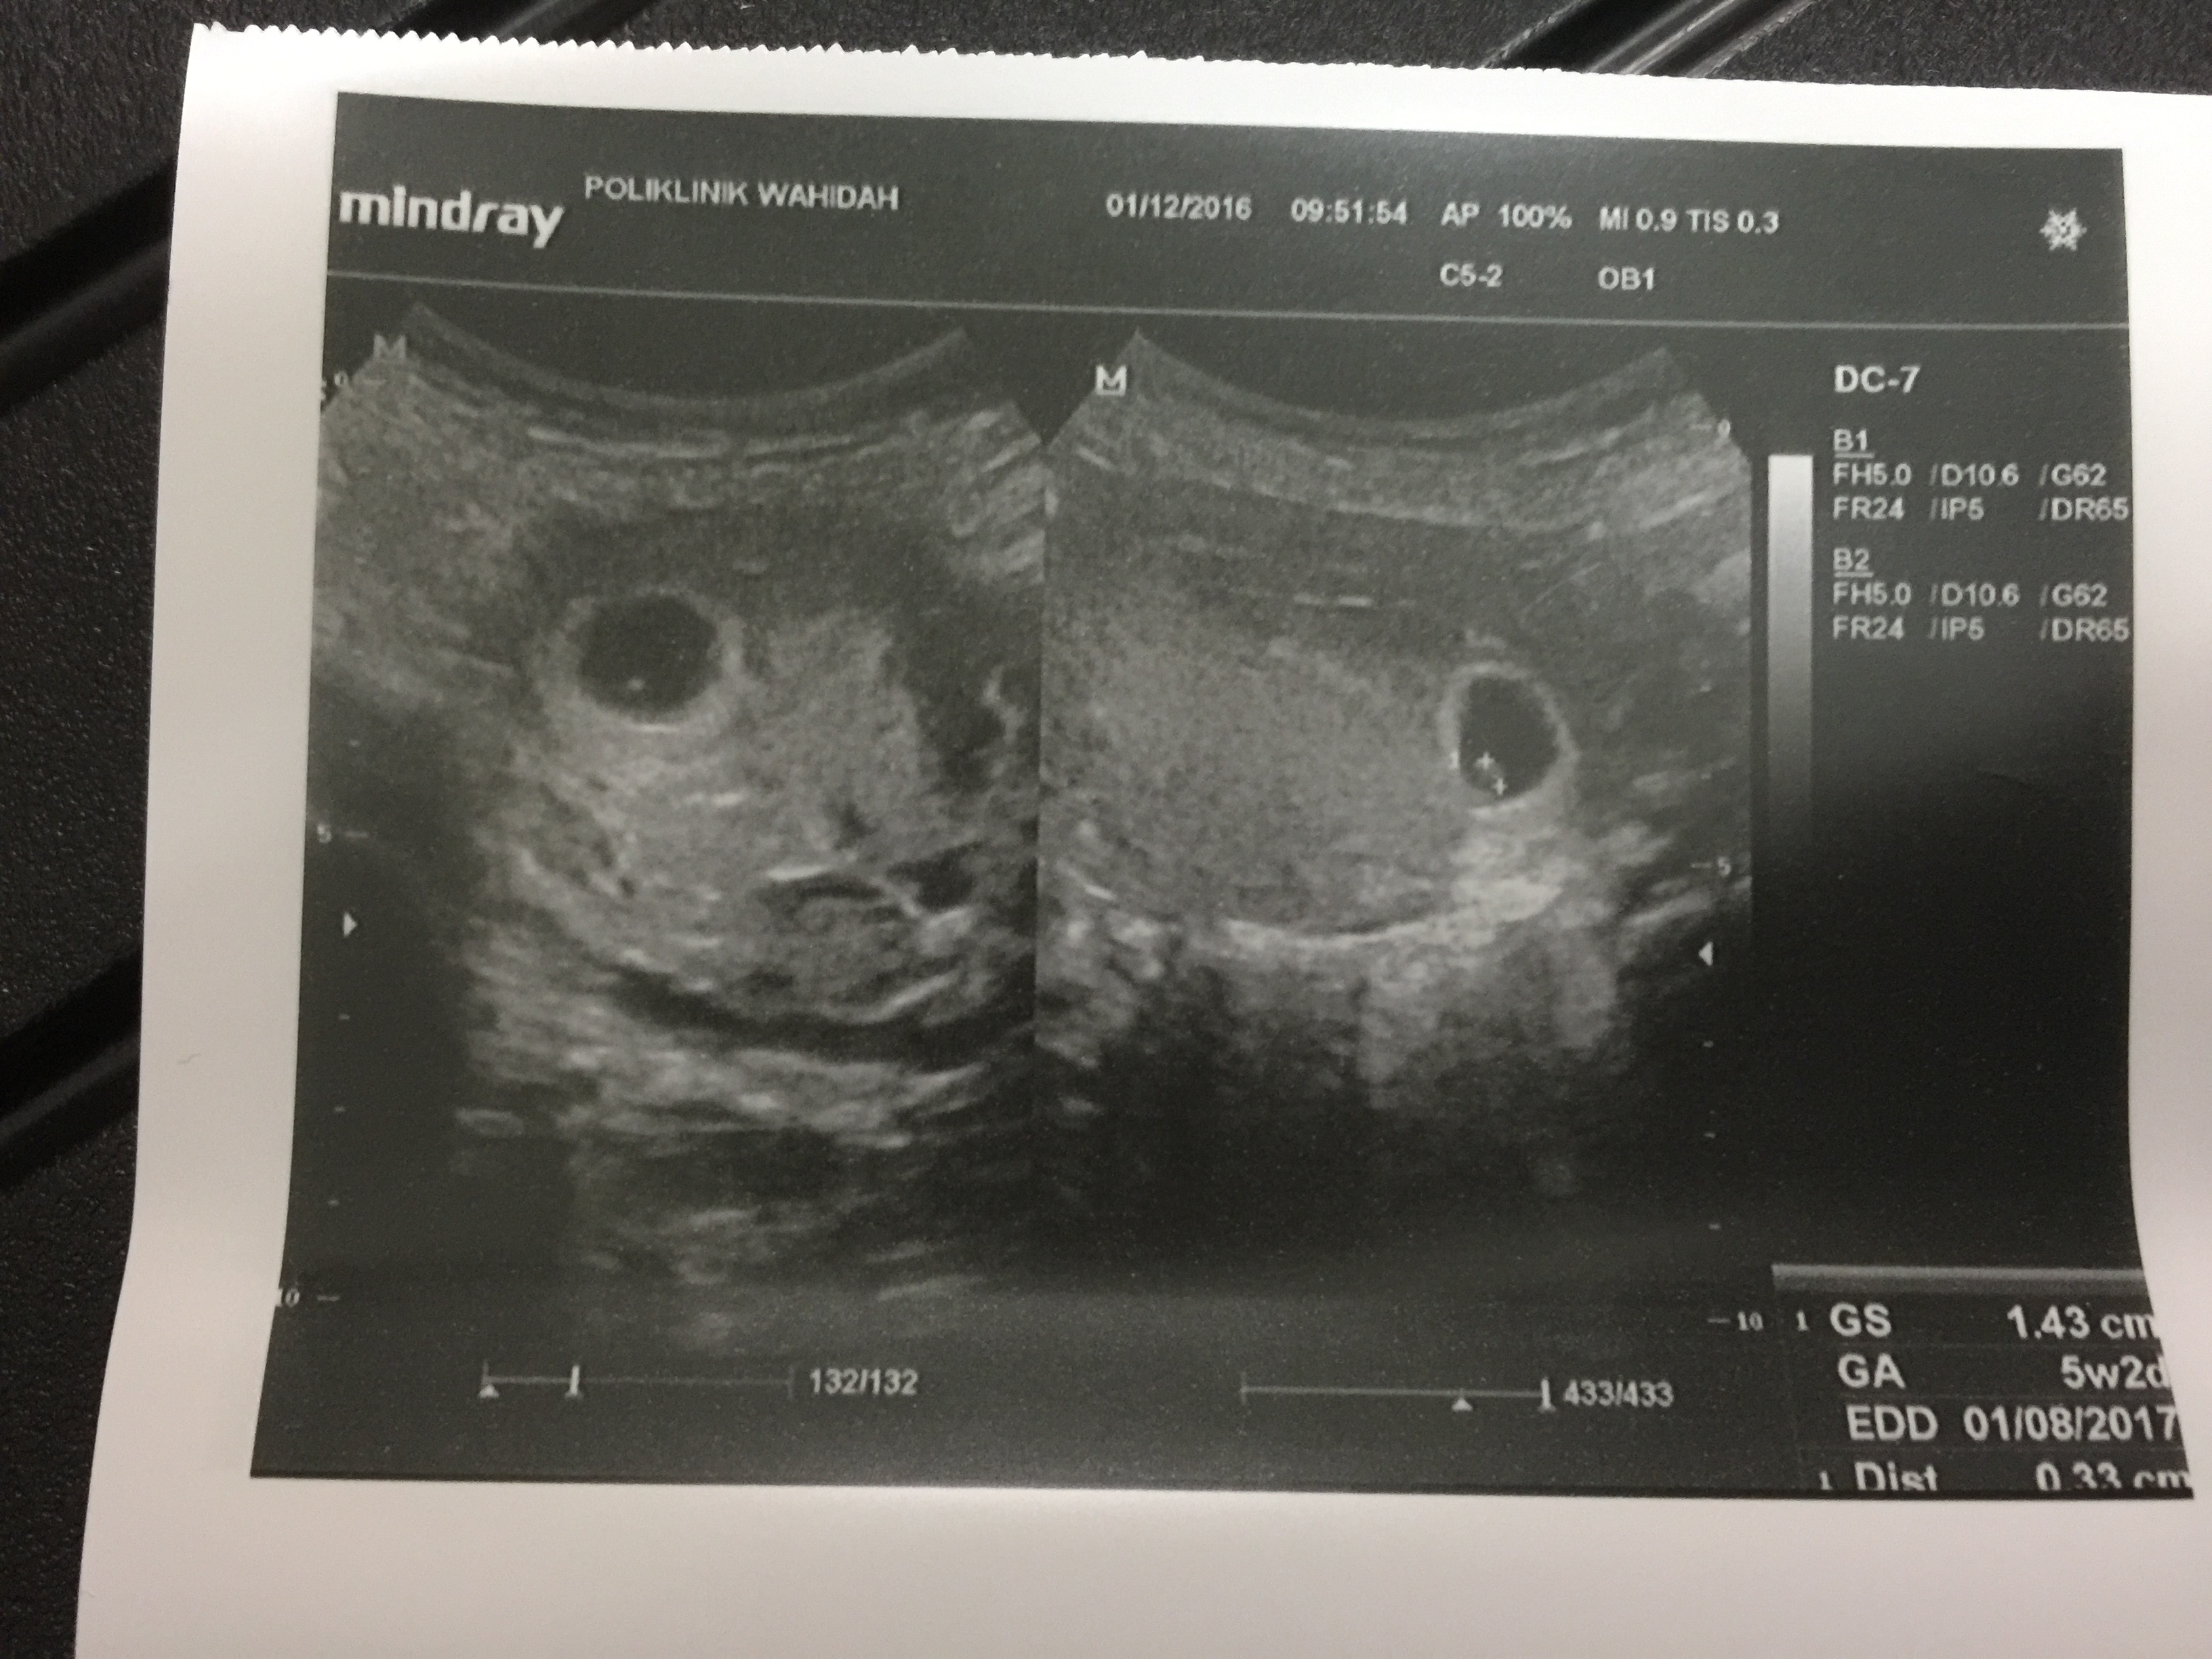

- Scan dibuat pada awalnya di Poliklinik Wahidah pada 1 December

Minggu ke – 6

Minggu ke-6

Gambar scan pada 5 week